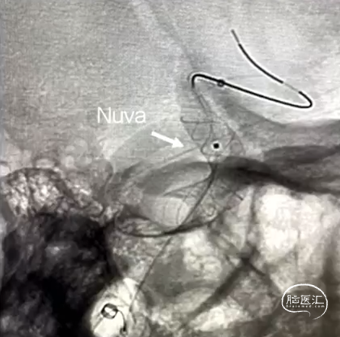

Nuva®血流导向密网支架联合弹簧圈栓塞治疗。

利用微导丝引导XT-27支架微导管置于大脑中动脉远端,然后将泰杰伟业TJED-D-5.0-14 Nuva®血流导向密网支架(预期血管直径和长度4.5mm*19mm)沿着支架微导管顺利输送到位。

缓慢回撤微导管,在颈内动脉末端处,影像下观察支架头端轻松打开,确认支架远端锚定区域,完成远端定位后,采用推拉结合方式缓慢稳定释放Nuva®支架至完全覆盖动脉瘤瘤颈口,并确保支架贴合打开情况良好。

继续缓慢释放Nuva®支架,在血管过弯处及支架尾端释放时注意随时调整系统张力,确保支架完全打开。

完全释放支架后,工作位造影可见支架显影清晰,形态良好,无贴壁不良,遂采取固定输送导丝,向前推送微导管,待微导管穿过装置后,将输送导丝远端回撤入微导管内,撤出支架输送系统。

为保证Nuva®血流导向密网支架的充分贴壁,支架完全释放后,微导丝弓背进入,进行支架内充分“按摩”,使之充分贴壁。

术后工作位及多角度观察,可见Nuva®血流导向密网支架打开良好、充分贴壁,颈内动脉血流正常,动脉瘤腔内可见明显造影剂滞留,分支血管保留良好,手术顺利结束。